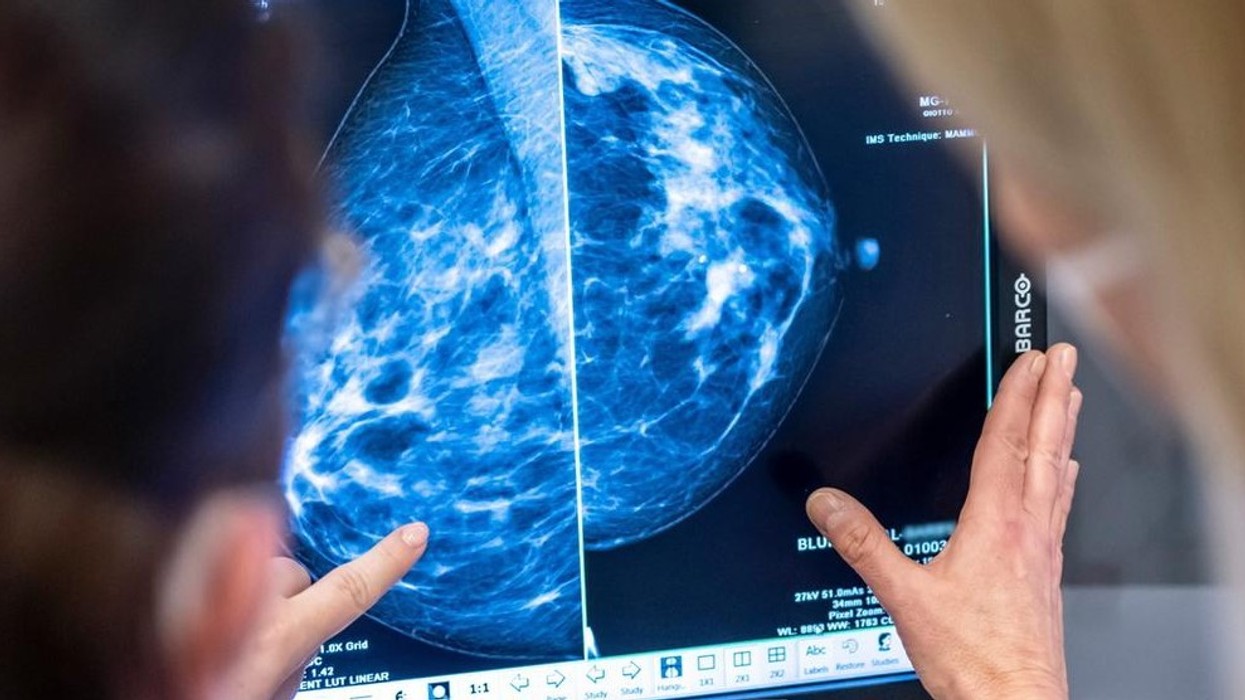

Afërsisht gjysma e të gjitha rasteve të reja përfshinin prostatën (79,600), gjirin (75,900), mushkëritë (58,300) ose zorrën e trashë dhe rektumin (55,300).